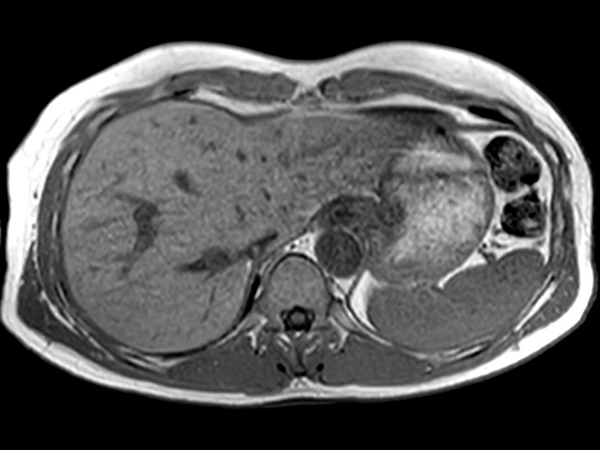

Axial T2w TSE MultiVane XD

-

Axial T2w SPIR MultiVane XD